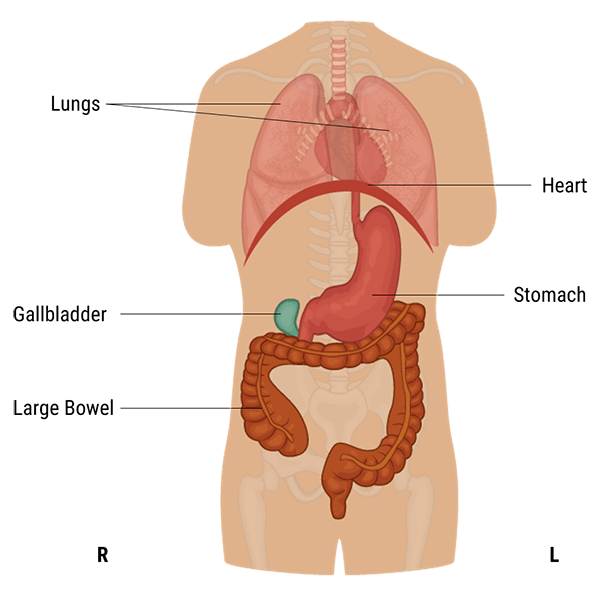

Asthenic

Whereas, asthenic individuals have a long, thin, and lean chest with the diaphragm, stomach, gall-bladder, and transverse colon situated lower down than hypersthenic and sthenic types. In the erect position, the stomach and transverse colon descend into the pelvis.

The radiographer has to take all these variations into account while positioning the patient for imaging.

Finally, hyposthenic individuals are similar to those of the asthenic type but stomach, intestines, and gallbladder are situated higher in the abdomen. They are characterized by a long, shallow thorax, a long thoracic cavity, a long, narrow abdominal cavity, and a slender build.

Hyposthenic and sthenic patients have very similar organ placement. Little or no manipulation of the grid, milliamperage, source-to-image distance (SID), or kilovolts peak are needed because these technical factors are almost interchangeable for hyposthenic and sthenic patients.

On the other hand, the radiographer has to increase these technical factors for hypersthenic patients and to decrease them for asthenic patients to improve the image quality. Let’s see the difference in the image clarity below.